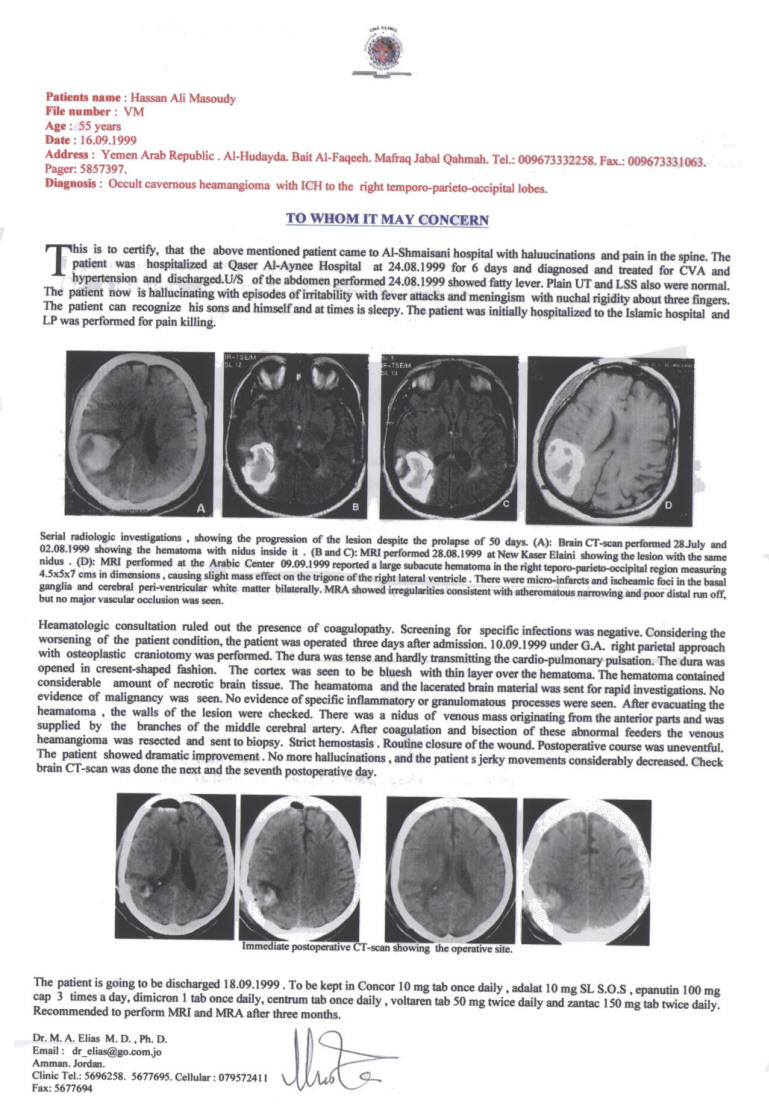

10-SEPTEMBER-1999 HASAN ALI MASOUDY 55 YEARS AVM RIGHT

PARIETO-OCCIPITAL LOBES WITH ICH. |